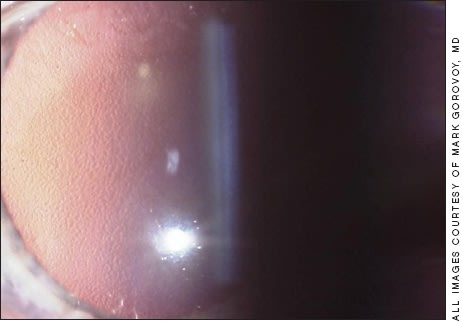

Fuchs' dystrophy (Figure 1), a genetic disorder of the Descemet's/endothelium complex, is almost always bilateral and is diagnosed by the presence of Descemet's guttata, typically in the pupillary axis. It is the most common diagnosis leading to cornea transplant in the western world, but rare in Asia.

Figure 1. Fuchs' dystrophy. Confluent dense gutta seen on red reflex are consistent with 20/40 to 20/50 vision. This is best treated with DSAEK after — or combined with — lens surgery.

Endothelial specular photography exquisitely documents the guttata as "black holes" replacing the endothelial cells. Often asymptomatic and discovered on routine slit-lamp exam, its early symptoms of diminished visual quality are caused by the disruptive visual quality of the guttata itself. Over time, the guttata become more confluent, more visually disruptive and eventually endothelial function becomes compromised, leading to frank edema.

It is the authors' experience that dense guttata by itself without edema decreases Snellen acuity to the 20/50 range and loss exceeding that level is best explained by comorbid disease. Fuchs' dystrophy, even when totally asymptomatic, has significant adverse clinical ramifications for patients contemplating anterior segment surgery, especially cataract surgery or LASIK.